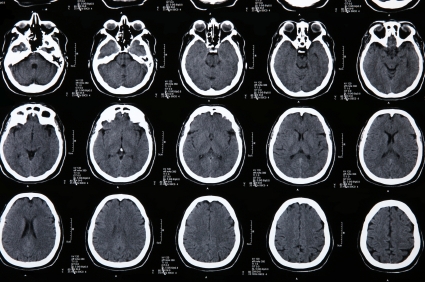

При подозрении на инсульт, пациент должен быть срочно госпитализирован и обследован. В диагностике обычно используется компьютерная томография, магнитно-резонансная томография. При отсутствии возможности проведения этих методов, диагностика менее достоверна и является результатом анализа клинической картины, данных спинномозговой пункции (в ликворе присутствует кровь), эхоэнцефалоскопии, дуплексного сканирования и церебральной ангиографии. Также необходимо исследовать: электролиты сыворотки крови, показатели функции почек, ЭКГ, маркеры ишемии миокарда, клинический анализ крови, протромбиновый индекс, насыщение крови кислородом.

Медицинские процедуры, проводимые при заболевании инсульт: Спиральная компьютерная томография, Магнитно-резонансная томография, Биохимический анализ крови, Клинический анализ крови, ЭКГ, Рентген, Спинальная пункция, Эхоэнцефалография, Дуплексное сканирование брахиоцефальных артерий (БЦА), Ангиография, Протромбиновое время, Протромбиновый индекс, Исследование газов крови